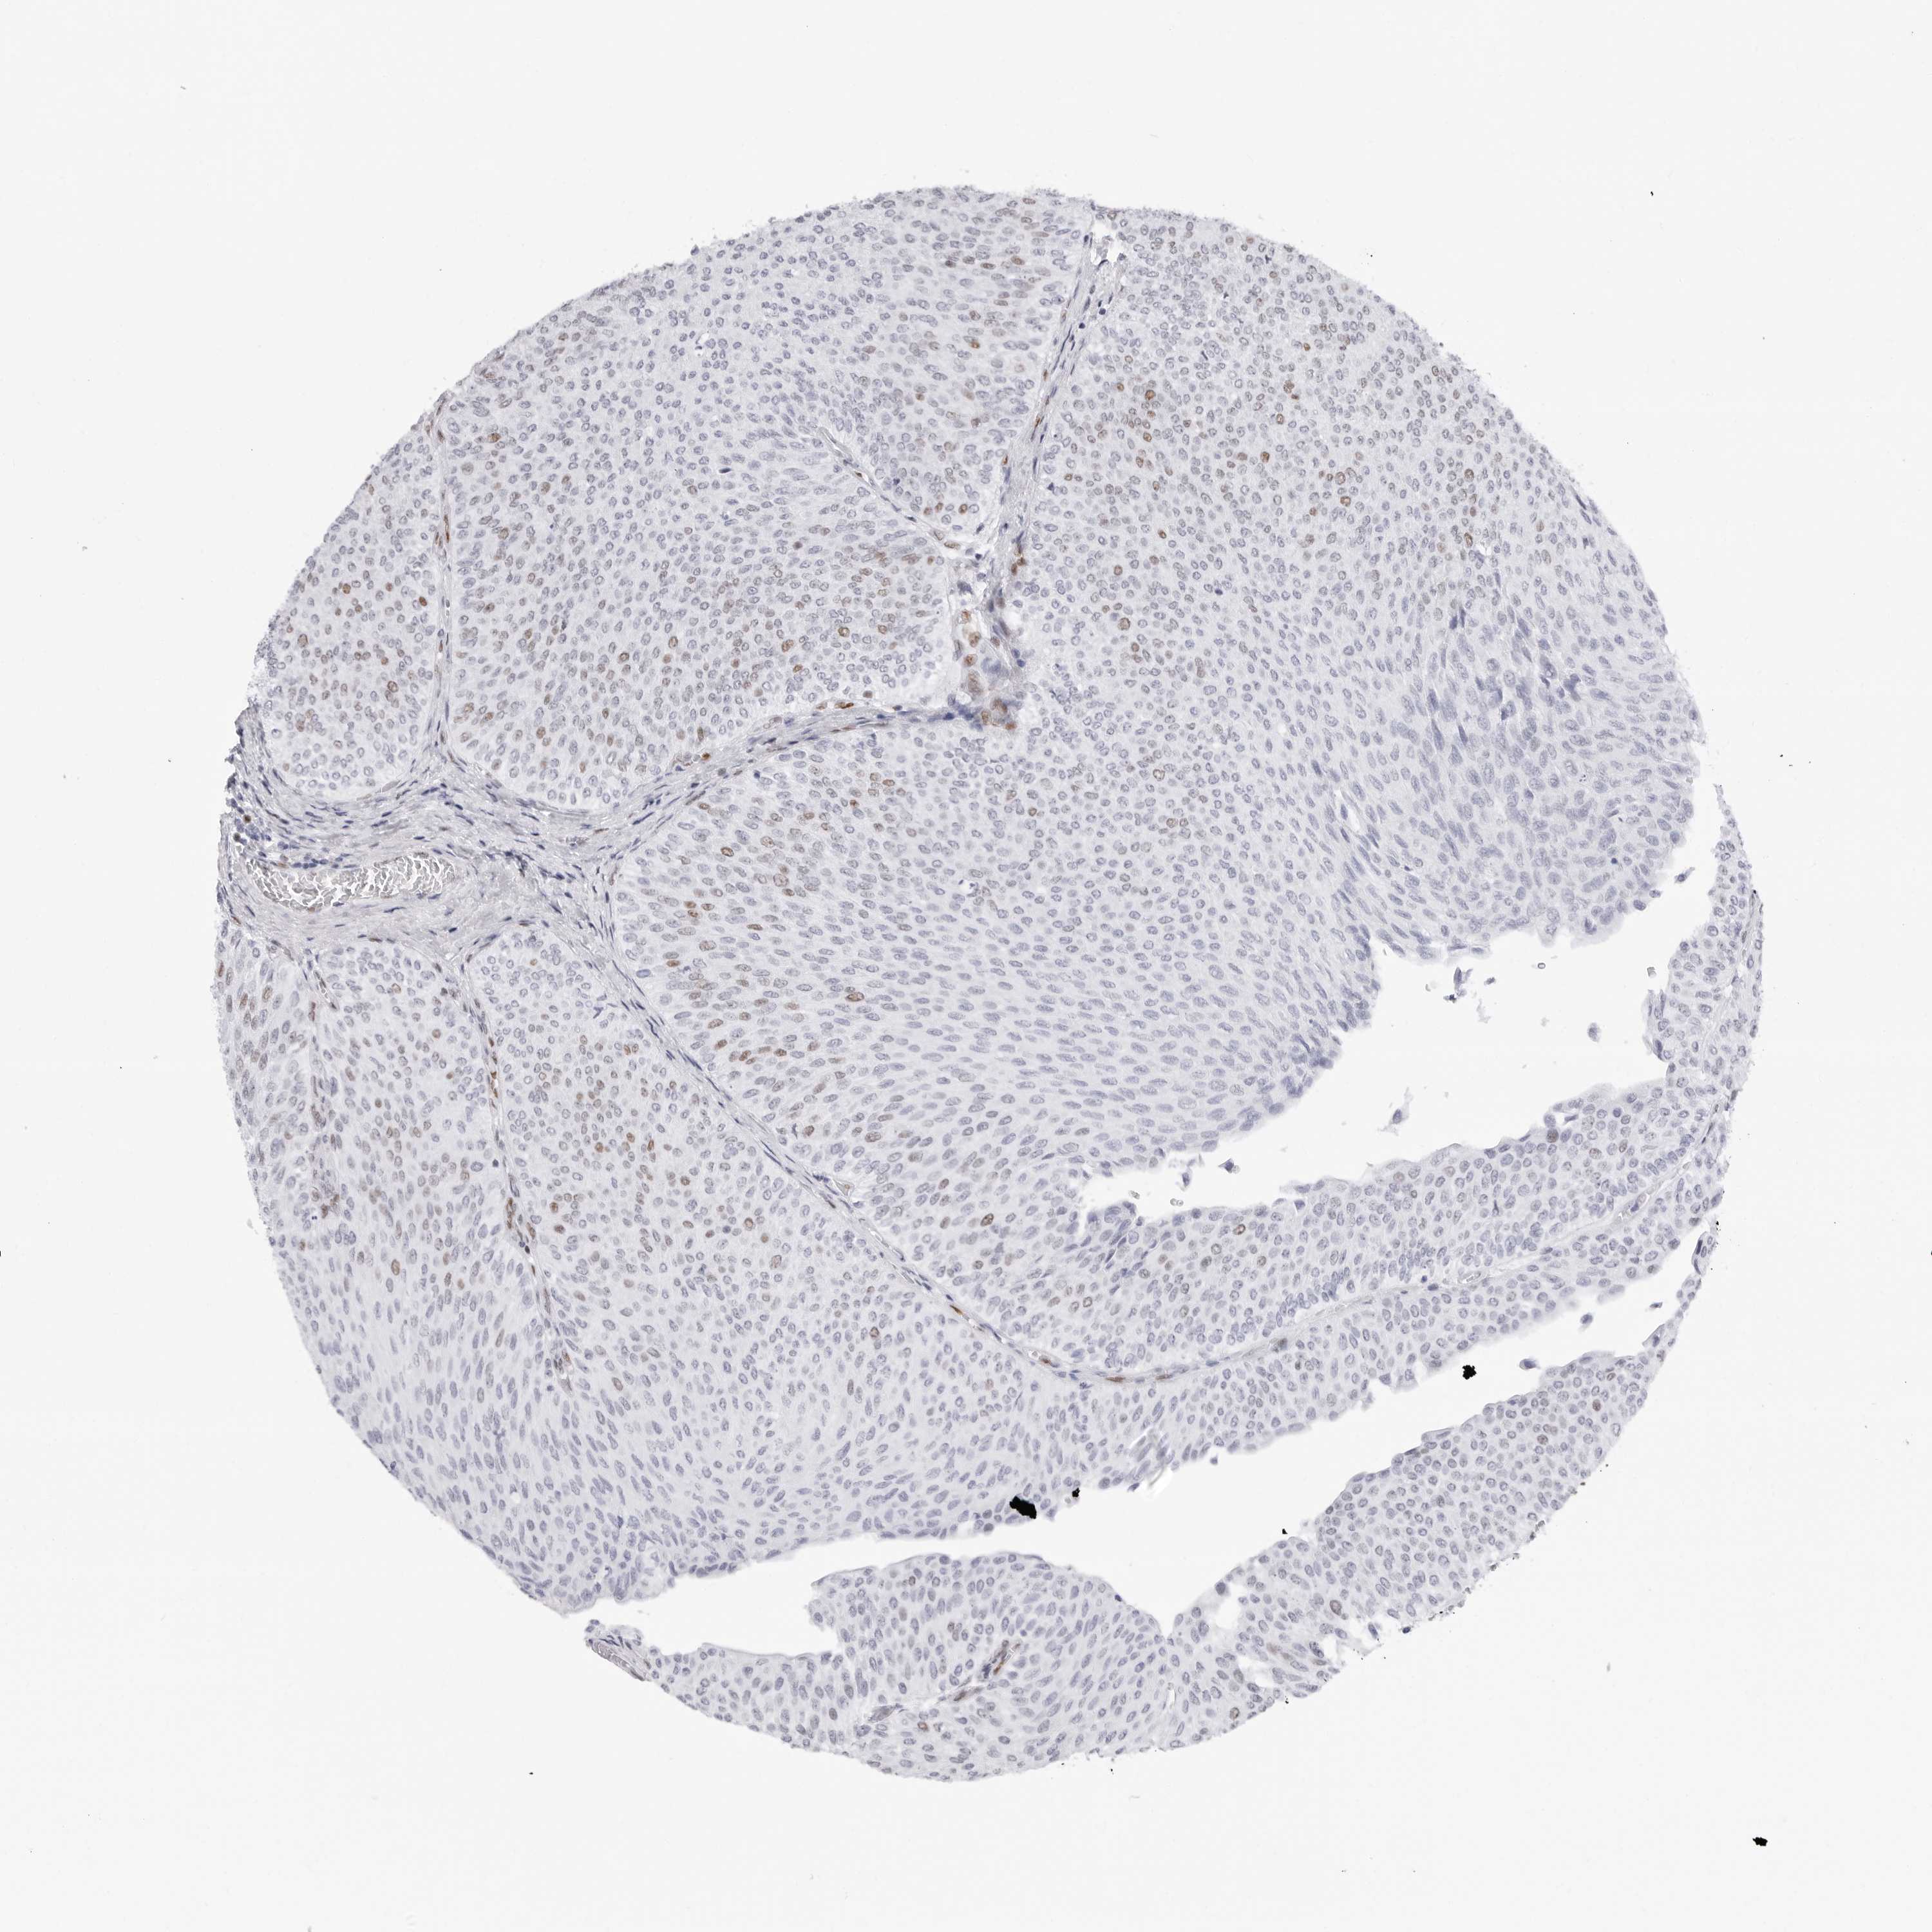

UROTHELIAL CANCER - Protein expressioni

A mouse-over function shows sample information and annotation data. Click on an image to view it in a full screen mode. Samples can be filtered based on level of antibody staining by selecting one or several of the following categories: high, medium, low and not detected. The assay and annotation is described here.

Note that samples used for immunohistochemistry by the Human Protein Atlas do not correspond to samples in the TCGA dataset.

Antibody stainingi

Antibody staining in the annotated cell types in the current human tissue is reported as not detected, low, medium, or high, based on conventional immunohistochemistry profiling in selected tissues. This score is based on the combination of the staining intensity and fraction of stained cells.

Each image is clickable and will lead to virtual microscopy that enables deeper exploration of all samples and also displays staining intensity scores, fraction scores and subcellular localization as well as patient and tissue information for each sample.

Antibody HPA028136

Antibody HPA030518

Antibody HPA030520

Staining

High

Medium

Low

Not detected

Intensity

Strong

Moderate

Weak

Negative

Quantity

>75%

75%-25%

<25%

None

Location

Nuclear

Cytoplasmic/membranous

Cytoplasmic/membranous,nuclear

Urothelial carcinoma, Low grade

Urothelial carcinoma, High grade